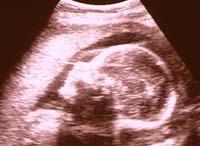

26-я неделя беременности

Впервые открываются глаза. Плод способен реагировать учащением сердцебиения на освещение передней брюшной стенки матери и реагировать на движение иглы при амниоцентезе

Достаточной зрелости достигают структуры, ответственные за центральную регуляцию дыхания. Это обеспечивает возможность их немедленного включения в работу после рождения ребенка. Если роды произойдут на 26 неделе, то у ребенка есть шансы выжить при условии содержания его в специальном кювезе.

Длина плода около 35 см, а его вес примерно 0,7 кг.